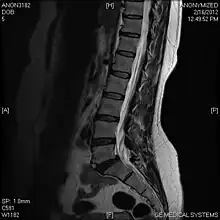

Limbus vertebra

A limbus vertebra is a bone tubercle formed by bone trauma on a vertebral body, bearing a radiographic similarity to a vertebral fracture. The anterior-superior corner of a single vertebra is the common site for this defect although it can also be seen at the inferior corner as well as the posterior or anterior margin. Anatomically, it is assumed to be an intra-vertebral body herniation of the disc material occurring during adolescent growth spurt when the ring apophysis has not yet fused. It was first described by Schmorl in 1927[1] and later in detail by Leif Sward and Adad Baranto.

Viewed in a lateral radiograph, it appears as a triangular shaped bone fragment, not unlike an anterior lip fracture, but with softer edges.

Limbus vertebra is not always symptomatic, but severe cases may lead to more serious pathological conditions and chronic pain. In rare instances, a posterior limbus vertebra has been described causing radiculopathy due to nerve root compression. [2]